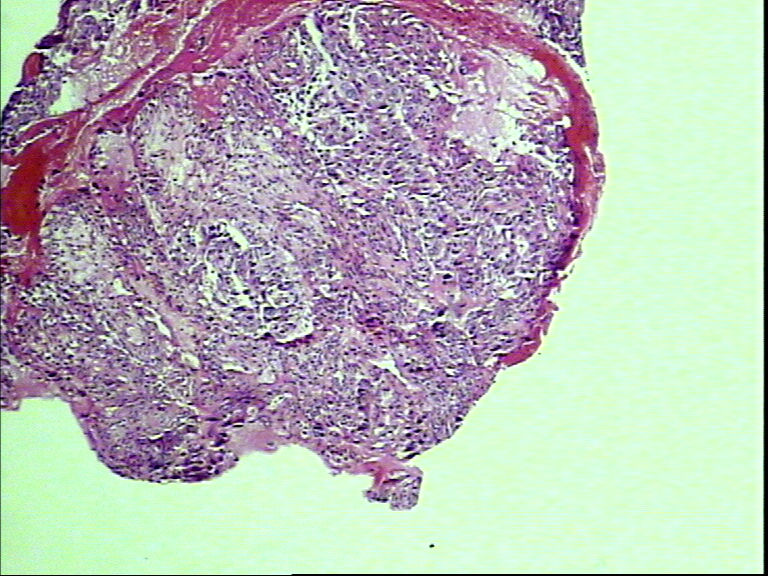

支气管活检,女性,65岁

• 支气管活检,女性,65岁图1

图1

鳞癌?腺癌?

鳞状细胞癌

组织太少,考虑鳞癌(建议再检)。

就本例而言基本肯定是鳞状细胞癌,退一步讲是腺癌的话,也不需再次活检了,排除小细胞癌了,不影响治疗方案了,只要其他情况还好的话,手术治疗是首选了。